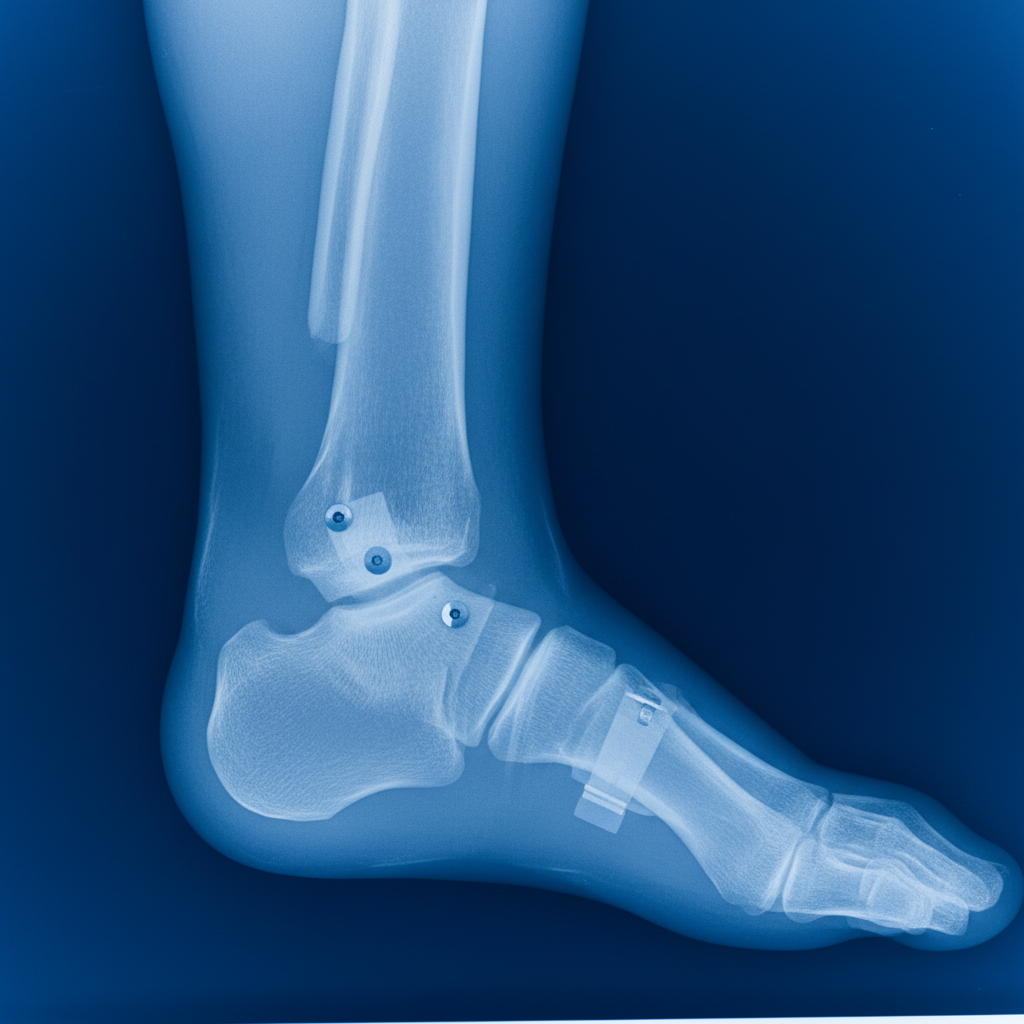

골절 진단서부터 수술 기록지, 입퇴원 기록, 외래 진료 기록, 처방전, 영상 자료(X-ray, MRI 등)까지 모든 의료 기록은 빠짐없이 보관해야 합니다. 이 모든 기록이 외측복사골절 후유장해를 증명하는 핵심적인 증거가 되기 때문이에요. 혹시 모를 상황에 대비해서 사본을 여러 개 만들어두는 것도 좋은 방법이에요. - 전문가와 반드시 상담하세요.